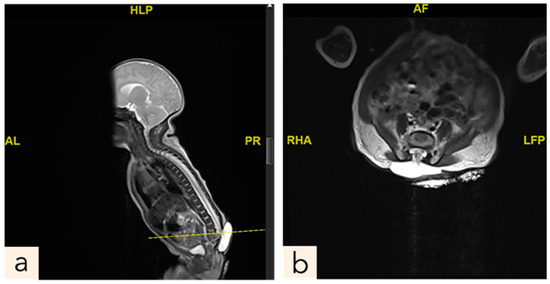

2.1. Patient 1